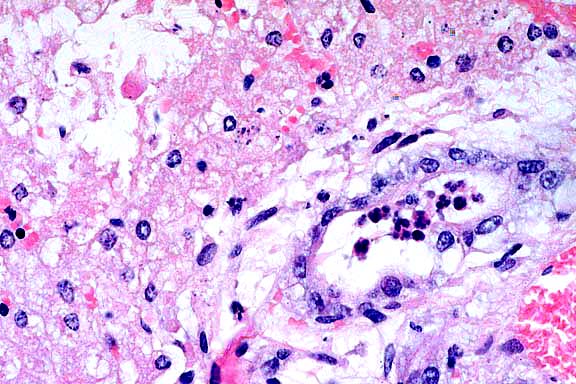

- The liver has severe, nearly massive, centrilobular and midzonal

hepatocellular necrosis together with severe periportal to bridging

fibrosis and biliary hyperplasia. Approximately 10-15% of the

hepatocytes remain. In addition to necrosis, most centrilobular

regions have severe hemorrhage. Some hepatocytes that remain

in periportal zones are large and have big, vesicular nuclei

(karyomegaly). There is fibrosis and biliary hyperplasia that

bridges portal areas. Fibrosis breaches the limiting plates and

extends into hepatic lobules. The periportal zones have mild

to moderate sized accumulations of macrophages admixed with a

few lymphocytes. Many of the macrophages have pale, brown cytoplasmic

pigment.

2x

obj.

- Case 21-3. Liver. There is diffuse centrilobular to

submassive hepatocellular necrosis.

20x

- Case 21-3. Liver. There is proliferation of periportal

fibroblasts and bile duct epithelial cells, with adjacent necrotic

hepatocytes.

- AFIP Diagnoses:

- 1. Liver: Necrosis, centrilobular to submassive, with hemorrhage

and intrahistiocytic light greenish-brown pigment, Dorset sheep,

ovine.

2. Liver: Biliary hyperplasia and bridging portal fibrosis, diffuse,

mild to moderate.

-